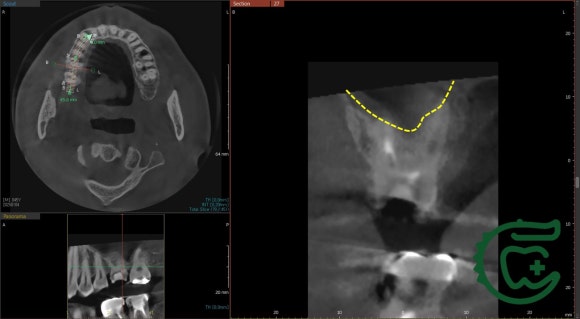

상악동에는 염증이 꽉 찬 상태.

(=윗 어금니와 코 사이, 광대 밑에 있는 빈공간)

물론,

치아에서 기원한 염증이 아닐 수도 있습니다.

비염이 있거나 코감기에 든 상태라면

CT 상에서 이렇게 보일 수 있죠.

이전 치과들에서 신경치료를 지속했음에도

뾰족하게 해결이 안되었던 이유는

바로 숨어있던 신경관에 있었습니다.

미세 현미경 하에서 이전 치료들에서 놓친

신경관을 찾아 청소해주니,

그 즉시 증상도 사라지고

상악동 내의 염증 소견도 사라졌네요.